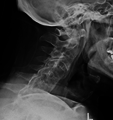

Fracture of the T5 and C7 vertebra due to trauma in a person with ankylosing spondylitis as seen on a CT scan

Prognosis is related to disease severity.[7] AS can range from mild to progressively debilitating and from medically controlled to refractory. Some cases may have times of active inflammation followed by times of remission resulting in minimal disability while others never have times of remission and have acute inflammation and pain, leading to significant disability.[7] As the disease progresses, it can cause the vertebrae and the lumbosacral joint to ossify, resulting in the fusion of the spine.[24] This places the spine in a vulnerable state because it becomes one bone, which causes it to lose its range of motion as well as putting it at risk for spinal fractures. This not only limits mobility but reduces the affected person's quality of life. Complete fusion of the spine can lead to a reduced range of motion and increased pain, as well as total joint destruction which could lead to a joint replacement.[25]

Osteoporosis is common in ankylosing spondylitis, both from chronic systemic inflammation and decreased mobility resulting from AS. Over a long-term period, osteopenia or osteoporosis of the AP spine may occur, causing eventual compression fractures and a back "hump".[26] Hyperkyphosis from ankylosing spondylitis can also lead to impairment in mobility and balance, as well as impaired peripheral vision, which increases the risk of falls which can cause fracture of already-fragile vertebrae.[26] Typical signs of progressed AS are the visible formation of syndesmophytes on X-rays and abnormal bone outgrowths similar to osteophytes affecting the spine. In compression fractures of the vertebrae, paresthesia is a complication due to the inflammation of the tissue surrounding nerves.